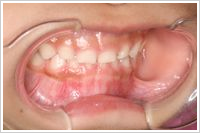

●症例(3歳10ヶ月 女の子 主訴:受け口)

治療期間:8ヶ月 治療費用:¥116,000(税別)

副作用・リスク:歯ぐきが痛くなることがある

軟性材料で作られたパナシールドを使用しました。口の大きさにあわせて後縁部分を2mm短くしました。昼間1時間と就寝時に装着します。最初の1~2週間はよだれがだらだらと出てきたり、うまく装着できず口から飛び出すことがありますが次第に慣れてきます。月に1回装置の調整を行いました。8ヶ月後には受け口が改善され正常な咬み合わせになりました。